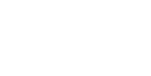

Otoskleroz Nedir? Kulak kireçlenmesi ya da tıbbi adıyla otoskleroz, orta kulaktaki kemikçiklerden, iç kulağa en yakın kemik olan stapes (üzengi) kemiğinde meydana gelen kemik yapım ve yıkımıyla ilgili bir bozukluk sonucu oluşan bir hastalıktır. Üzengi kemiğinde meydana gelen kireçlenme odağı, orta kulaktaki kemikçiklerin titreşimini önler. Kemikler titreşemeyince ses iç kulağa iletilemez. Otoskleroz Belirtileri Nelerdir? Otoskleroz…